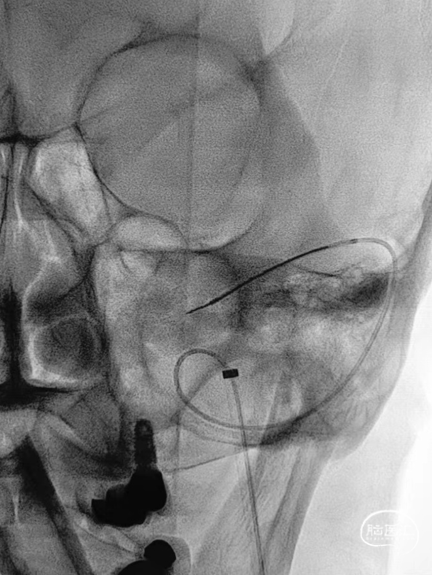

➤DSA

6F 长鞘导引至左侧颈内静脉末端。

测压导丝对横窦至乙状窦进行测压,静脉压差<2mmHg,未对狭窄段进行球囊扩张。

6F 长鞘导引至左侧乙状窦。

交换Command 18导丝超选至左侧横窦,将Echelon-10微导管置入静脉窦憩室。

路图下,沿Command 18导丝将8×40mm Xpert Pro支架输送至乙状窦,使用支架近远端marker点进行准确定位,整个推送过程顺利,无明显阻力。

Xpert Pro支架未展开状态下在憩室内尝试使用弹簧圈进行填塞,发现成篮困难。

随即释放Xpert Pro支架以覆盖憩室开口,支架打开后显影清晰,贴壁良好。使用微导管穿出支架网孔,并置入憩室内进行弹簧圈填塞。单微导管填塞过程弹簧圈成篮较为困难。

使用双导管继续在Xpert Pro支架辅助下进行弹簧圈填塞,再次造影显示:憩室内血液已完全阻滞,未见显影。

Xpert Pro支架在乙状窦内形态良好。静脉窦憩室闭塞完全。